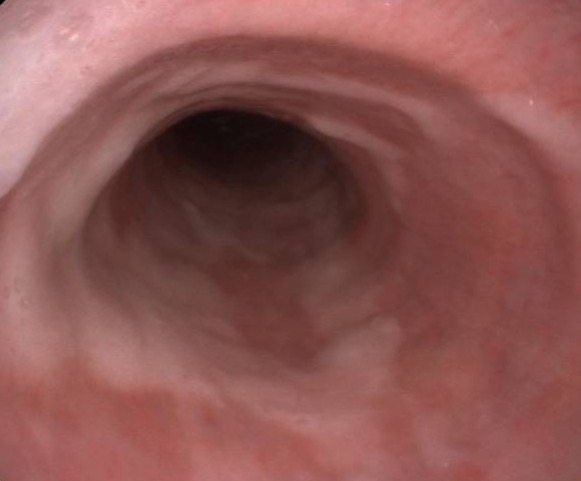

Gastroskopie: Untersuchung des Magens

Eine Gastroskopie beim Pferd ist die wichtigste Methode zur Diagnose von Magengeschwüren und anderen Erkrankungen des oberen Verdauungstraktes.

Wichtig: Das Pferd muss 12 Stunden vor der Untersuchung hungern und in den letzten 3 Stunden kein Wasseraufnehmen. Nur so ist der Magen frei einsehbar.